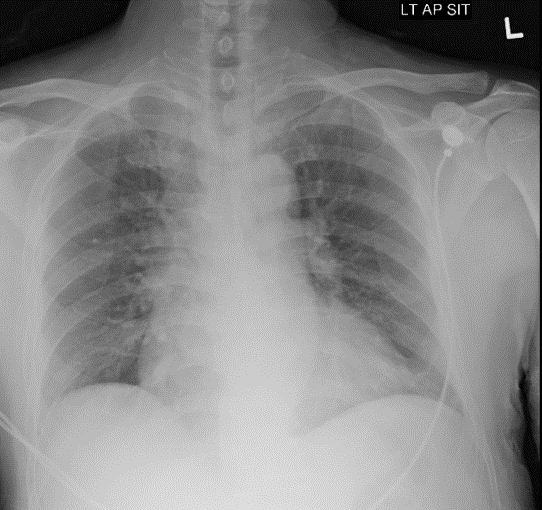

CXR is clear